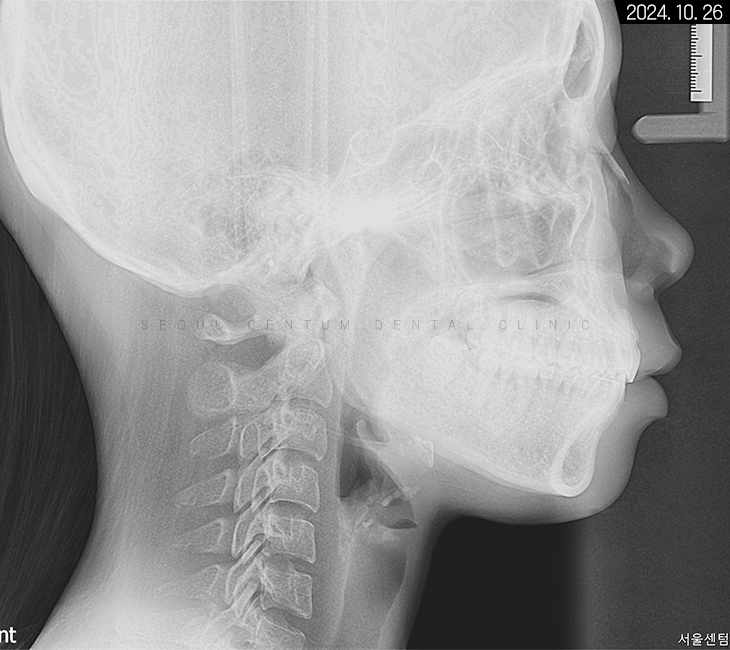

세팔로 사진을 봤을 때에도

눈에 바로 띌 정도로

수평피개가 좋아졌고

윗입술의 도톰함도 해소된 게 보였습니다.

그리고 아래턱이 후하방으로 빠져 있던 것도

돌출입 교정을 통해

전상방으로 비율 좋게 돌아왔습니다.

아직도 살짝 에스테틱 라인에 걸쳐 있지만,

외국인이라는 것을 감안하고 보면

자연스러운 정도의 전돌 양상입니다.

초기와 비교한 모습

치아 교정 후에 확실히 구강 구조가 가지런해졌으며

각도, 전돌 등 정상 범주를 벗어난 부분까지

바르게 만들어져서 훨씬 보기 좋은 모습입니다.